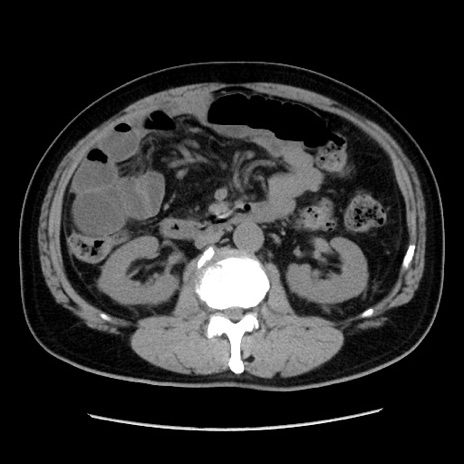

症例16(横断像)

【症例】 70歳代男性

【主訴】 腹痛、嘔吐

【現病歴】 約1ヶ月前より間欠的に腹痛と嘔吐あり、当院消化器内科を受診したところCTで多発する肝臓のLDAを指摘され、精査中であった。以降は消化器症状は安定していたが、2日前より嘔気と腹痛があり、同日より排便・排ガスが消失した。改善認めず、 本日、救急外来を受診した。

【既往歴】 大腸ポリープ切除後。

【身体所見】意識清明・会話良好、BT 36.3℃、BP 127/80mmHg、 P 80bpm、腹部:膨満あり、平坦・軟、上腹部正中および下腹部正中に圧痛あり、反跳痛なし、筋性防御なし。

【データ】WBC 7200、CRP 0.77